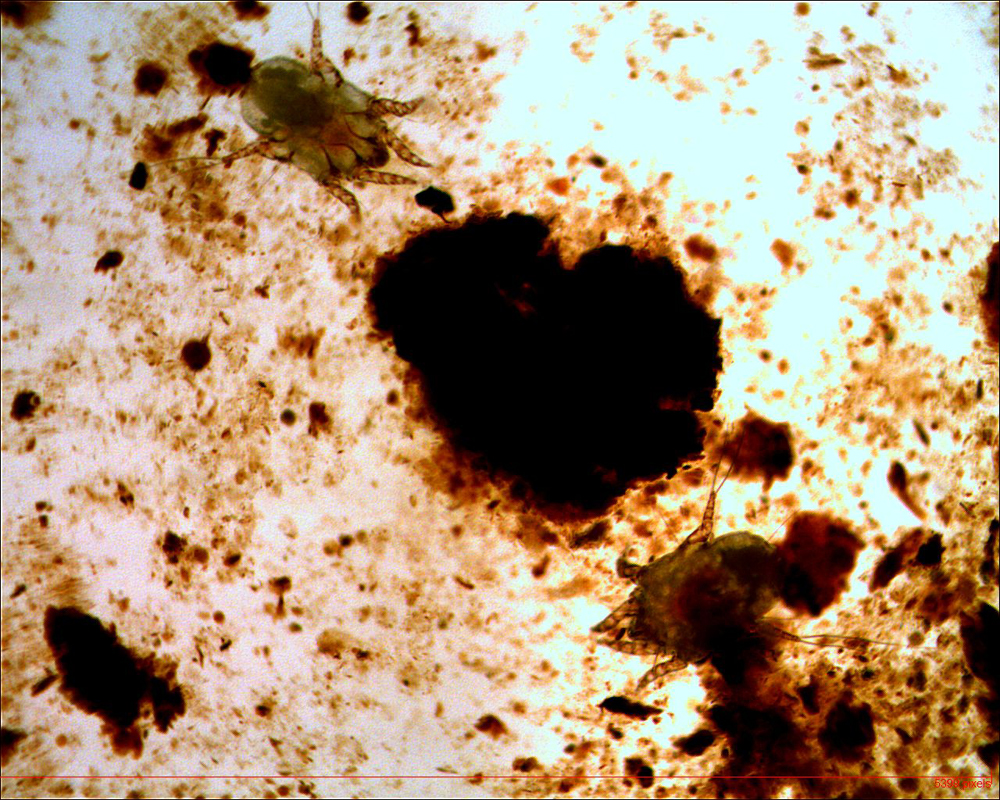

Het gaat zowel bij de hond als de kat om de Otodectes cynotis, ze zijn grijs-wit en leven op de huid in en rond de gehoorgang. De cyclus van de oormijt duurt 3 weken en speelt zich geheel op de gastheer af. Ze leven van huidschilfers en van de huidvloeistof.

De mijten beschadigen dus de huid in de gehoorgang, wat irritatie geeft. Hierdoor zal de productie van oorsmeer gaan toenemen. Echter een grote hoeveelheid donker oorsmeer is zeker niet bewijzend voor oormijt, het wordt namelijk bij veel oorontstekingen gezien op basis van vele andere oorzaken.

De enige manier om de diagnose te stellen is een inspectie van een gehoorgang met een otoscoop. De mijten zijn zelden in de schelp al te zien, in dat geval is een loep wel aan te raden.